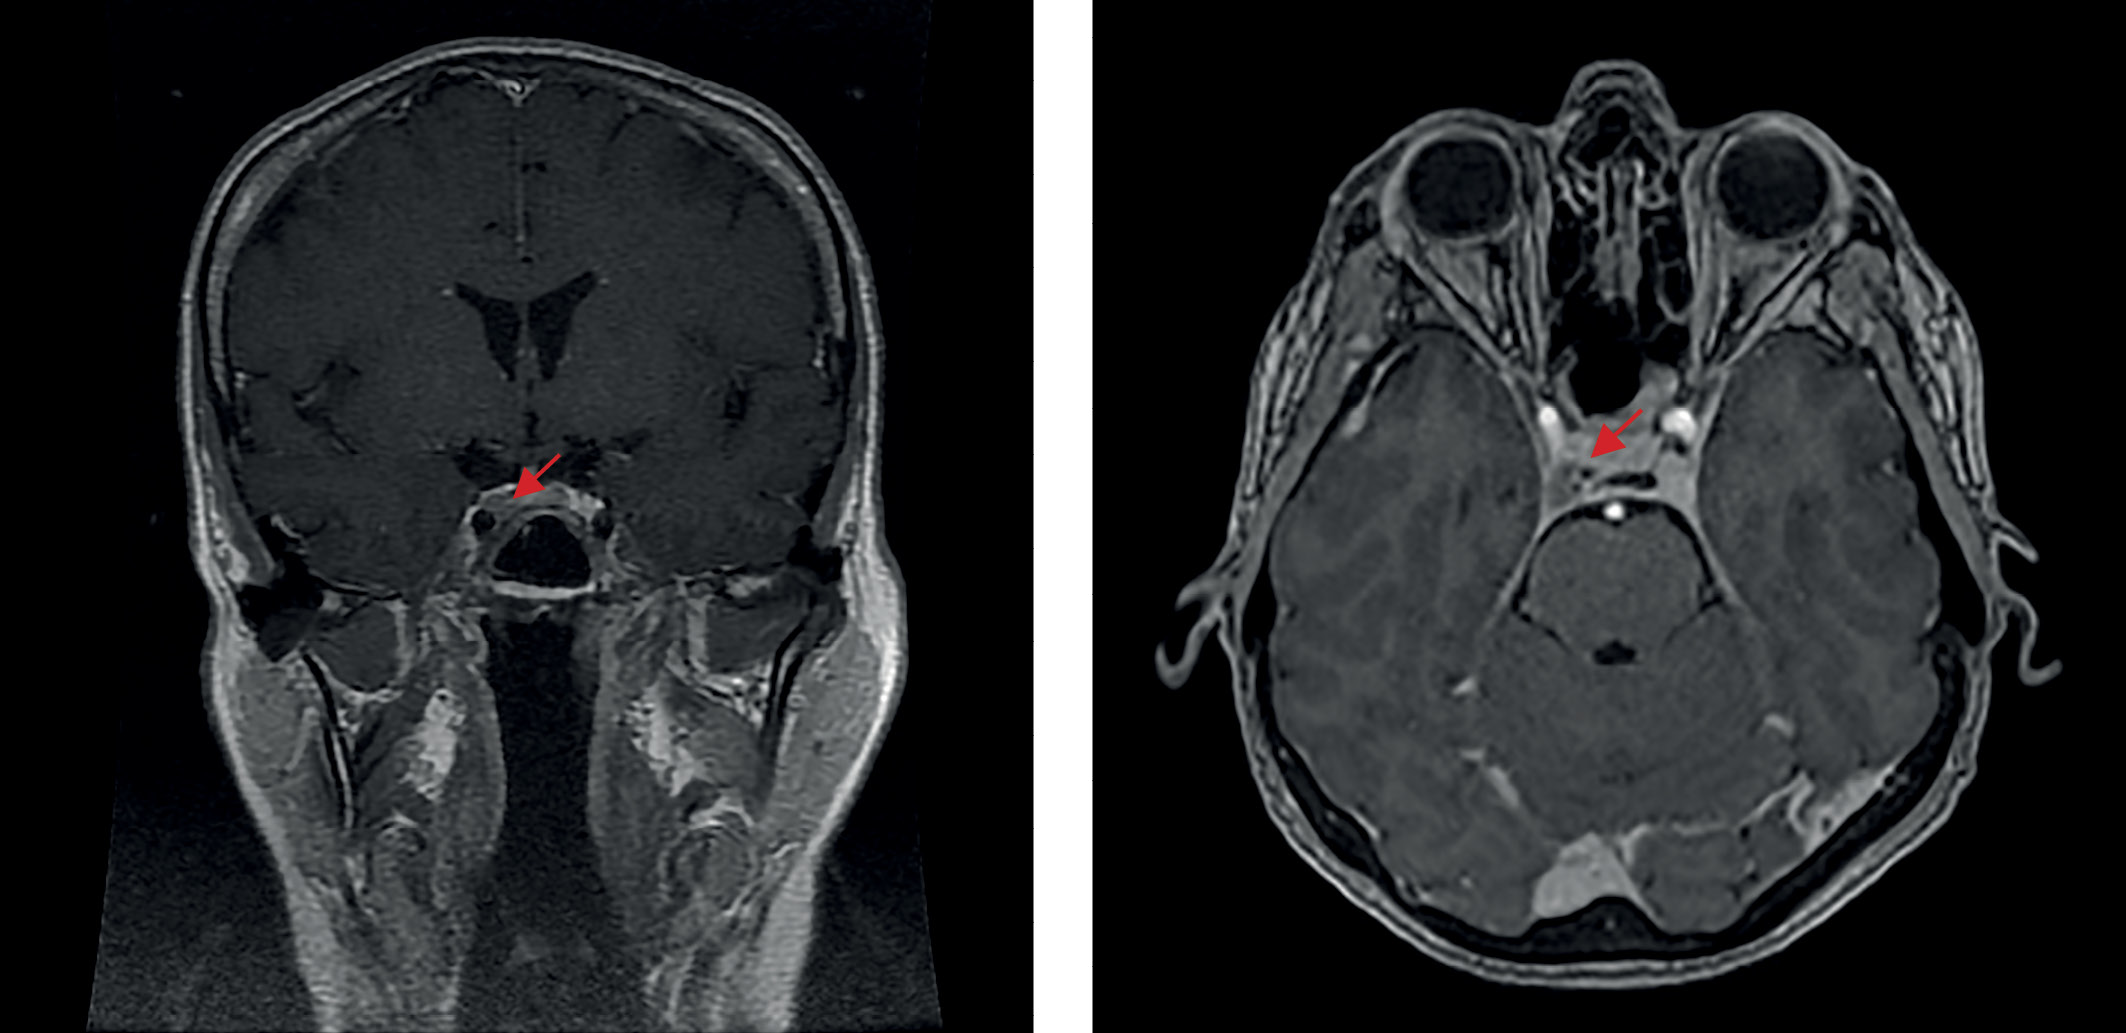

С января 2022 г. снова стала отмечать ухудшение состояния, когда появились признаки гиперкортицизма. При амбулаторном обследовании: кортизол в суточной моче — 2664,0 нмоль/сут, АКТГ — 123 пг/мл, кортизол в сыворотке крови — 940 нмоль/л, кортизол в слюне в 23.00 — 29,9 нмоль/л. В марте 2022 г. в ходе госпитализации в отделение нейроэндокринологии ФГБУ «НМИЦ эндокринологии» Минздрава России лабораторно подтвержден рецидив эндогенного гиперкортицизма: кортизол свободный в моче — 2557,6 нмоль/сут (100–379), кортизол слюны в 23.00 — 17,52 нмоль/л (0,5–9,65), кортизол крови вечером — 704,4 нмоль/л (64–327), АКТГ утром — 102,8 пг/мл (7,2–63,3), АКТГ вечером — 71,7 пг/мл (2–25,5). По данным МРТ головного мозга (рис. 4): эндо-латероселлярная аденома гипофиза с распространением вправо по шкале Knosp-IV, размерами 8×12×10 мм (умеренное увеличение размеров в сравнении с исследованием от 20.11.2021 г.). 29 марта 2022 г. выполнено повторное оперативное лечение в объеме трансназального транссфеноидального удаления аденомы гипофиза. По результату ИГХ-исследования удаленной ткани: плотногранулированная кортикотропинома (оценка экспрессии Ki-67 в данном случае не проводилась). В послеоперационном периоде состояние пациентки удовлетворительное, выраженных жалоб не предъявляла.

Рисунок 4. МРТ головного мозга перед второй операцией (повторной трансназальной аденомэктомией), 2022 г.

4. Рисунок 4. МРТ головного мозга перед второй операцией (повторной трансназальной аденомэктомией), 2022 г.